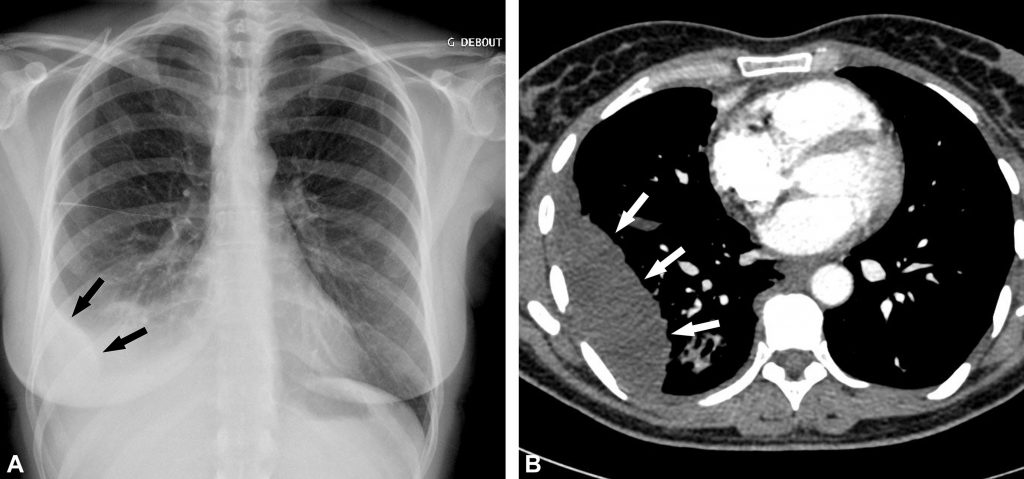

Fig. 91.3. Radiographie de face debout d’un hydropneumothorax droit.

La limite supérieure de l’épanchement liquidien droit est horizontale (flèches), ce qui suggère un niveau hydroaérique. Le niveau hydroaérique est confirmé par la présence d’un pneumothorax droit associé (têtes de flèches).

Source : CERF, CNEBMN, 2022.